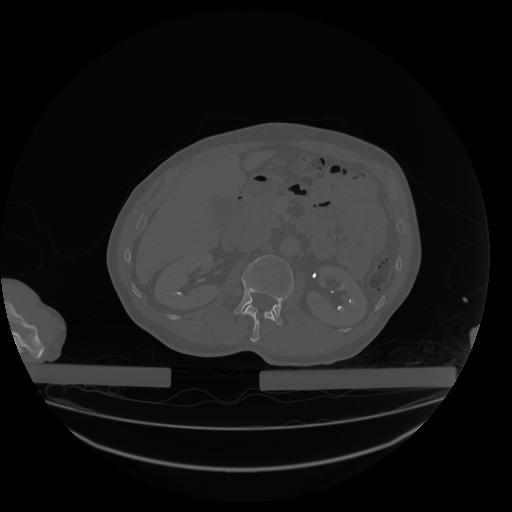

34 CUERPO,CE,Vol,1.0,CUERPO,,